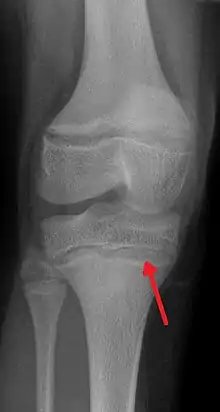

| An X-ray demonstrating the characteristic finding of lead poisoning in humans—dense metaphyseal lines | |

Exposure to lead can occur by contaminated air, water, dust, food, or consumer products.[2] Lead poisoning poses a significantly increased risk to children as they are far more likely to ingest lead indirectly by chewing on toys or other objects that are coated in lead paint.[2] The amount of lead that can be absorbed by children is also higher than that of adults. Exposure at work is a common cause of lead poisoning in adults with certain occupations at particular risk.[7] Diagnosis is typically by measurement of the blood lead level.[2] The Centers for Disease Control and Prevention (US) has set the upper limit for blood lead for adults at 10 µg/dl (10 µg/100 g) and for children at 3.5 µg/dl,[8] previously before October 2021 5 µg/dl[9][10] Elevated lead may also be detected by changes in red blood cells or dense lines in the bones of children as seen on X-ray.[4]

Blood lead levels are an indicator mainly of recent or current lead exposure, not of total body burden.[208] Lead in bones can be measured noninvasively by X-ray fluorescence; this may be the best measure of cumulative exposure and total body burden.[37] However, this method is not widely available and is mainly used for research rather than routine diagnosis.[103] Another radiographic sign of elevated lead levels is the presence of radiodense lines called lead lines at the metaphysis in the long bones of growing children, especially around the knees.[209] These lead lines, caused by increased calcification due to disrupted metabolism in the growing bones, become wider as the duration of lead exposure increases.[209] X-rays may also reveal lead-containing foreign materials such as paint chips in the gastrointestinal tract.[26][209]